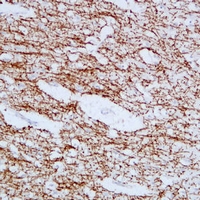

Immunohistochemical analysis of MBP staining in human brain formalin fixed paraffin embedded tissue section. The section was pre-treated using heat mediated antigen retrieval with sodium citrate buffer (pH 6.0). The section was then incubated with the antibody at room temperature and detected using an HRP conjugated compact polymer system. DAB was used as the chromogen. The section was then counterstained with haematoxylin and mounted with DPX. -